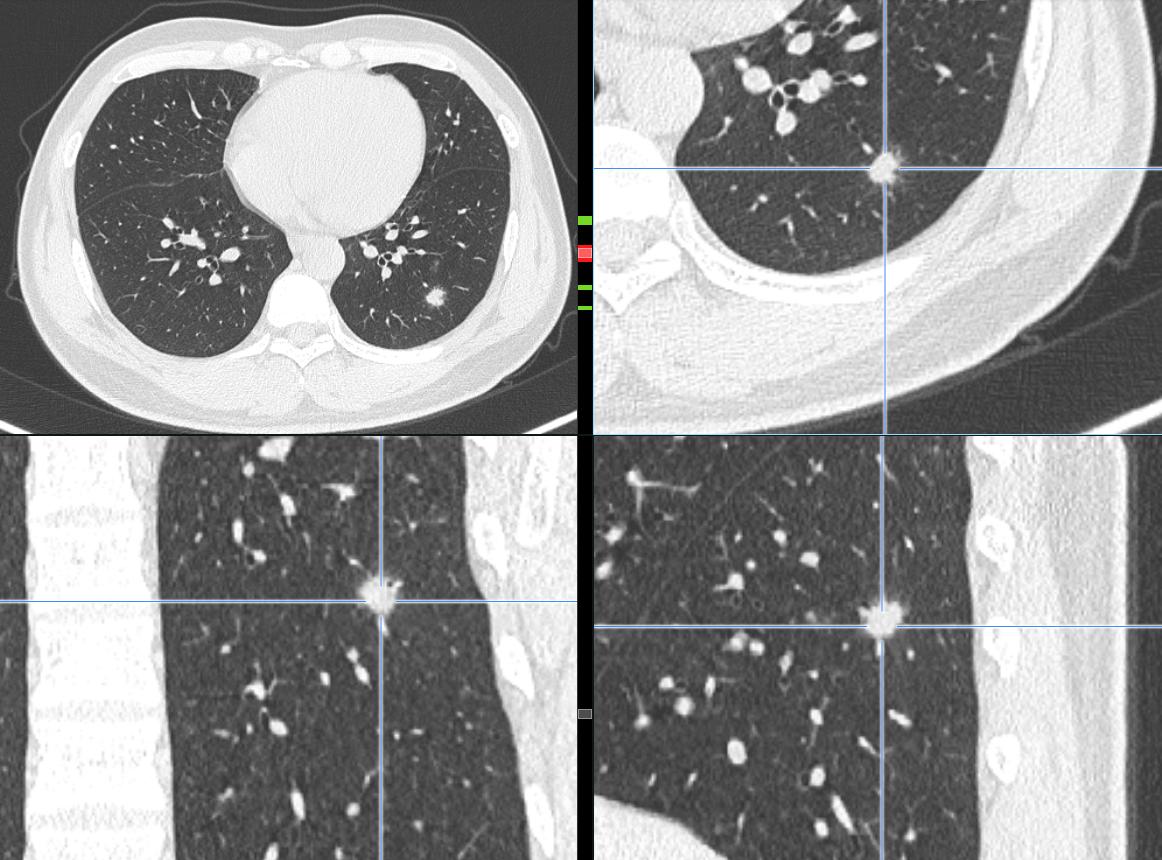

影像学是建立在高清影像的基础上的诊断,首先我们的图片要清楚,以下是患者家属提供的DICOM数据,分析时得到的图片。很多时候诊断不清楚,就是因为影像资料不清楚。

通过以上图片,病灶确实为实性结节,大小约1.0cm×0.9cm×1.0cm,呈浅分叶,周边可见毛刺,可见小血管穿入,但是影像学还是有一些不符合恶性肿瘤的特点:

1.病灶周边有一些渗出性改变。

2.相对1cm大小的肺结节来说,周边的毛刺有点长。

3.病灶及周边有扩张的支气管影。

4.病灶周边血管明显有贴边征象。

5.病灶两个月前 大小约0.6cm×0.8cm,这一点还是很重要的,如果我们在看诊过程中只带胶片,很难比较的。

6.双肺还有多发类似实性小结节,病灶均较为模糊,虽然是实性结节,但相对更趋于新发的可能,没有纤维化。